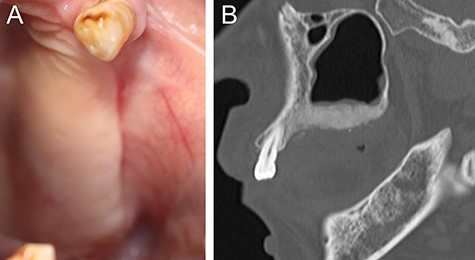

Sagittal section of CT image showing the maxillary bone with a ground glass appearance in distal regions from #24 part and bone resorption around #25 and #26.

A 69-year-old woman was referred to our hospital by a dentist at another hospital because of swelling in her left maxilla. There was the mobility of the left maxillary second premolar and first molar (FDI #25 and #26) and swelling of the surrounding gingiva. Computed tomography (CT) images revealed maxillary bone expansion with a ground glass appearance (Fig. 1). The patient had begun steroid therapy for polymyalgia rheumatica 4.5 years earlier. Since then she had been taking alendronate, one of the oral BPs, for the prevention of glucocorticoid-induced osteoporosis.